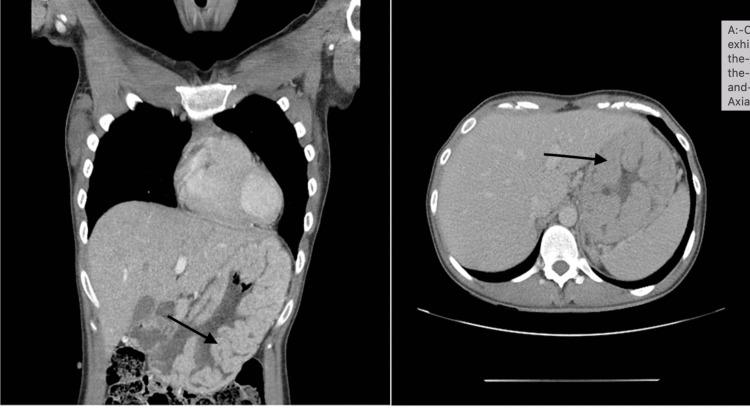

Ménétrier's disease is a rare, acquired, premalignant disorder of the stomach distinguished by hypertrophic giant mucosal folds in the proximal part of the stomach (body and fundus), diminished acid secretion and excessive mucous production, resulting in hypoalbuminemia. Menetrier's is also known as hypoproteinaemic hypertrophic gastropathy and giant hypertrophic gastritis. We present a case of four siblings who presented between 2010 and 2017 with symptomatic iron deficiency anaemia or upper gastrointestinal symptoms with confirmed Ménétrier's disease. The etiology of Ménétrier's disease is unknown but it has been linked to raised TGF-α (transforming growth factor alpha protein) in the gastric mucosa causing increased signalling of epidermal growth factor. It is also associated with infections such as cytomegalovirus and . Despite these associations, there have been cases without any of these viruses detected.  Diagnosis is usually made by barium swallow or endoscopic evaluation, which characteristically shows thickened gastric folds, while the biopsies' hallmark feature is massive foveolar hyperplasia. We present a case series of four siblings who presented between 2010 and 2017 with symptomatic iron deficiency anaemia or upper gastrointestinal symptoms with confirmed Ménétrier's disease.

梅内特里尔病是一种罕见的后天性癌前胃部疾病,其特征为胃近端(胃体和胃底)出现肥厚性巨大黏膜皱襞、胃酸分泌减少以及黏液分泌过多,从而导致低蛋白血症。梅内特里尔病也被称为低蛋白血症性肥厚性胃病和巨大肥厚性胃炎。我们报告了一个四兄弟姐妹的病例,他们在2010年至2017年间因有症状的缺铁性贫血或上消化道症状就诊,确诊为梅内特里尔病。梅内特里尔病的病因尚不清楚,但它与胃黏膜中转化生长因子α(TGF-α)水平升高有关,这会导致表皮生长因子信号增强。它还与巨细胞病毒等感染有关。尽管有这些关联,但也有未检测到任何这些病毒的病例。诊断通常通过钡餐或内镜评估进行,其特征性表现为胃皱襞增厚,而活检的标志性特征是大量小凹增生。我们报告了一个四兄弟姐妹的病例系列,他们在2010年至2017年间因有症状的缺铁性贫血或上消化道症状就诊,确诊为梅内特里尔病。